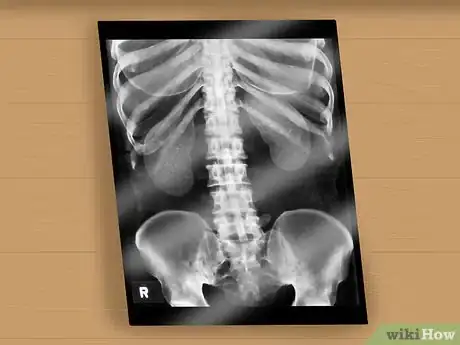

8Get a spinal column x-ray, MRI, or CT scan. Usually this is for spina bifida occulta (SBO), the mildest form of spina bifida, but it can confirm other types as well. The primary method of discovering forms of SBO that may cause problems is an x-ray that can detect a small gap or abnormality of the spine, or less often a spinal cord that is tethered, thickened, contains a fatty lump, is split in two, or connected to skin. This can also be detected using magnetic resonance imaging (MRI), or computed tomography (CT) scan. Most people with SBO don't have any problems. However, there may be some other associated symptoms with SBO, such as:

- Pain, numbness, or weakness in the back or legs

- Deformed legs, feet, back

- Change in bladder or bowel function[7]

4Ask for an internal scan for spina bifida. Scans that are postnatal, after the baby is born, are often the only way milder forms of spina bifida are discovered. An x-ray, MRI, or CT scan examination can be performed. This option is used primarily when the spina bifida symptoms are not clearly visible.